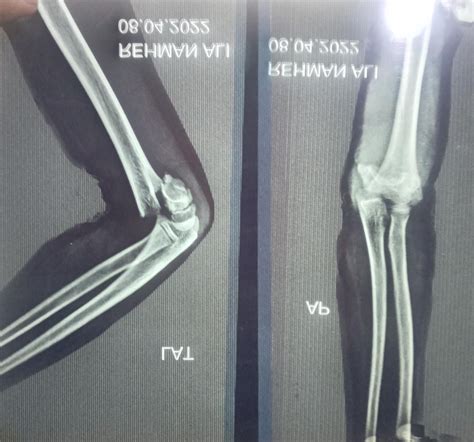

Diagnosing Supracondylar Humerus Fractures

Diagnosing a supracondylar humerus fracture involves a thorough physical examination and imaging studies. The healthcare provider will assess the elbow for signs of injury, such as swelling, deformity, and tenderness. Imaging studies, such as X-rays, are crucial for confirming the diagnosis and determining the type and severity of the fracture.

X-rays are typically taken from multiple angles to provide a comprehensive view of the fracture. In some cases, additional imaging studies, such as a CT scan or MRI, may be necessary to assess the extent of the injury and plan the appropriate treatment.